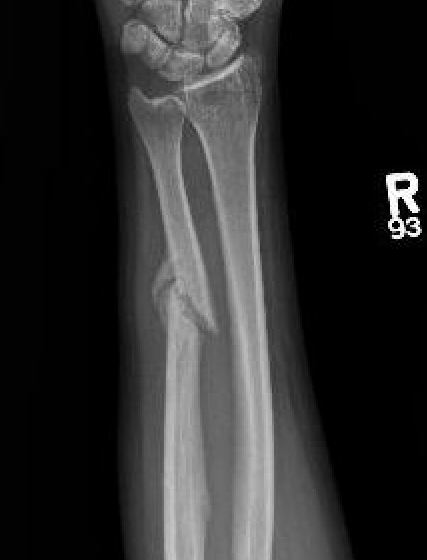

Distal 1/3

- < 50% displaced

- < 10 degrees angulation

- > 50% displacement

- > 10 degrees angulation